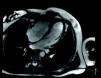

Ten days after discharge, the patient experienced recurrence of chest pain, with no fever. Control TTE showed RV apical hypokinesia and an apical mass of the same signal intensity as the myocardium with no cleavage plane between the mass and the myocardial wall (Figure 2). Pericardial thickening persisted with a moderate effusion. In the light of the new findings, the RV mass was considered to be a thrombus or tumor, or to be secondary to hypereosinophilic syndrome. Oral anticoagulation with warfarin was begun given the suspicion of a thrombus and the patient was transferred to Coimbra University Hospital for cardiac magnetic resonance imaging (CMRI) and endomyocardial biopsy (EMB). CMRI revealed marked thickening of the RV apex, of infiltrative appearance (Figure 3). Delayed enhancement showed heterogeneous areas of hyperintense signal in the RV apex, septal wall and LV apex, some of which had a subepicardial distribution. EMB revealed fragmentation of muscle bundles by eosinophils, with myocyte destruction and coagulation necrosis, compatible with eosinophilic endocarditis. The diagnosis of Loeffler's endocarditis was therefore established and treatment begun with oral prednisolone (1mg/kg/day), anticoagulation with warfarin being continued. During follow-up, the patient was completely free of pain, her eosinophil count normalized and the RV myocardial thickening disappeared (Figure 4), confirmed by CMRI (Figure 5). Anticoagulation was maintained for three months and corticosteroid therapy for six months. She subsequently had one episode of sustained back pain without hypereosinophilia or echocardiographic alterations, and was treated with corticosteroids for four weeks. The patient has been evaluated every six months by ECG, laboratory tests and TTE, and three years after beginning treatment, control CMRI shows her to be in complete remission.